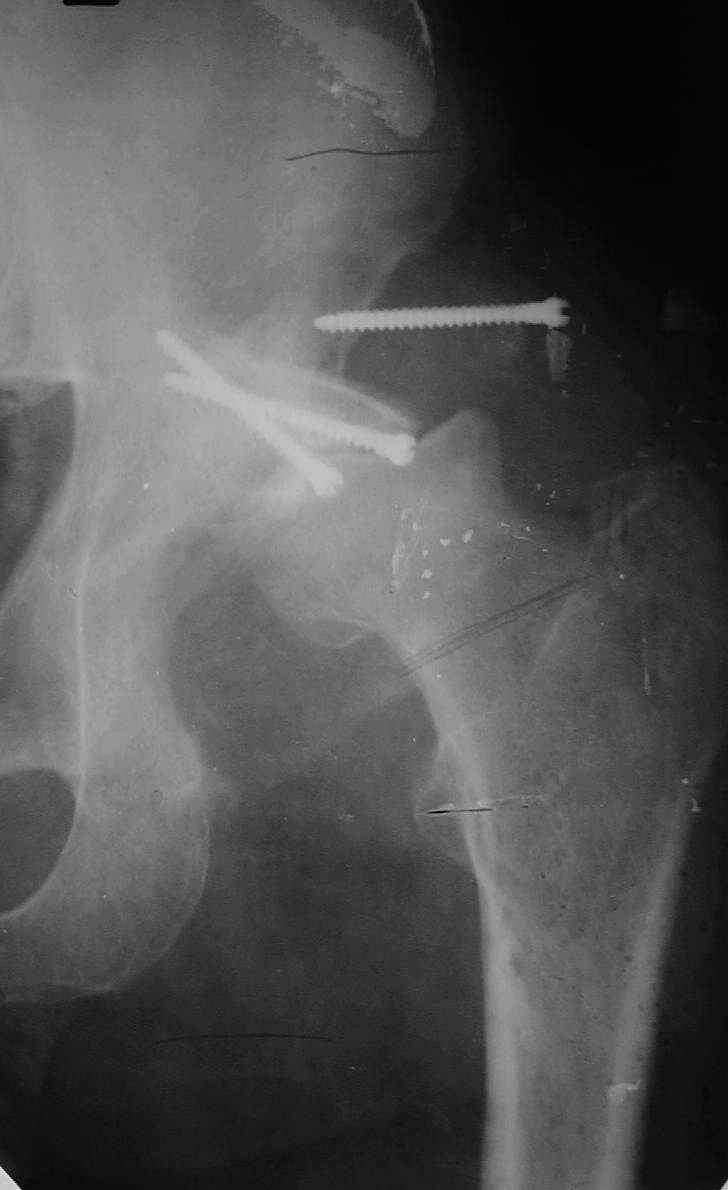

В институте совместно с фирмой Зиммер достаточно регулярно (практически ежемесячно) проводятся 2-х недельные циклы по различным вопросам эндопротезирования. Если есть возможность и желание, мы готовы поделиться с Вами нашим опытом, тем более есть что показать и что обсудить - в настоящее время ежедневно выполняется от 6 до 10 эндопротезирований коленного и тазобедренного сустава. В качестве примеров хочу показать 2 наблюдения, через 1 год и 5 лет после операции

С уважением, Р.Тихилов

1 год

5 лет